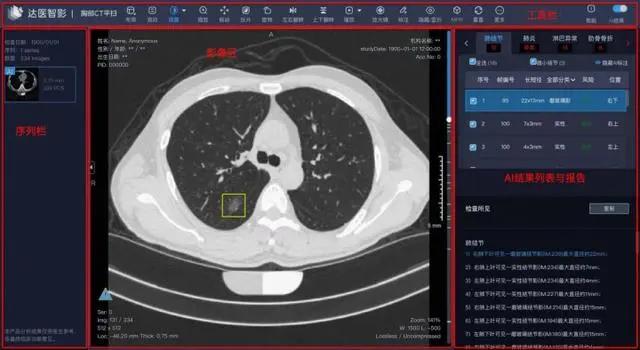

04 民间版AI早筛神器

讲真,虽然用AI来进行医疗影像检查,早已在人类的预料之中,但这个技术真正成熟,却是最近两三年的事。

这也是为什么,在阿里将这项成果的论文发表在《自然·医学》上后,很多审稿人都不相信这类技术已经成熟到足以胜过人类了,以至于质疑声不断。直到后来,阿里在法兰克福的节点上创建了一个可操作的demo,才消除了疑虑。

不过,或许令这些审稿人更难以相信的是,早在阿里推出PANDA之前,一个名叫coolwulf的中国“民间奇侠”,早在2018年就已经尝试用50张1080Ti搭建了一个初级的 GPU 运算集,乳腺癌的检测。

于是,在悲痛的驱使下,具有编程天赋的coolwulf,开始尝试打造一种专门用来“看片子”的AI,以便让那些无法及时就医的病人,提早得知病情。

尽管历经了这种种的局限与困难,当coolwulf最终完成了 AI 检测乳腺癌网站的搭建,并且向公众免费开放后,肿瘤识别的准确率,仍然达到了 90%。